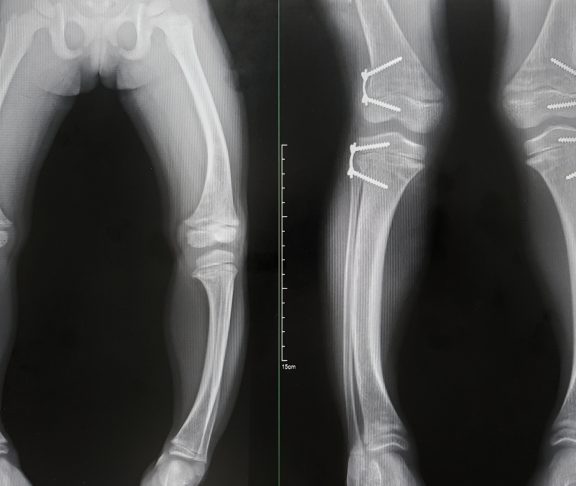

Gibt es in einer Familie bereits XLH-Betroffene, dann werden neu in diese Familie geborene Kinder in der Regel direkt auf die Erkrankung untersucht. Ist das nicht der Fall, werden betroffene Kinder meist klinisch auffällig, wenn sich der Laufbeginn verzögert, da die Knochen nicht stabil genug sind und die Kinder gehemmt sind, sie zu belasten. Sobald sie dann doch beginnen zu laufen, verformen sich durch die fehlende Aushärtung der wachsenden Knochen die Beine. In den meisten Fällen entwickeln sie ausgeprägte O-Beine, aber auch X-Beinstellungen treten auf. Durch die Störung im Knochenstoffwechsel ist zudem häufig auch das Wachstum verzögert. Außerdem härtet häufig der Zahnschmelz nicht richtig aus, was zu Zahnproblemen bis hin zu schmerzhaften Zahnabszessen führen kann. Im Moment gehen wir davon aus, dass bei 70% der Fälle bereits andere Familienmitglieder betroffen sind. 30% werden als spontane Varianten angesehen.

Ist die Diagnose gestellt, gibt es mittlerweile sehr gute Behandlungsmöglichkeiten. Früher war die einzige Möglichkeit die Gabe von Phosphat und aktivem Vitamin D. Das nicht sehr schmackhafte Phosphatpräparat musste mehrmals am Tag oral eingenommen werden, was für betroffene Kinder und ihre Eltern einen Kraftakt darstellte. Glücklicherweise gibt es seit einigen Jahren einen Antikörper, der an der Ursache der Erkrankung ansetzt und bereits in der frühen Kindheit eingesetzt werden kann. Dieser muss nur noch alle zwei Wochen per Injektion verabreicht werden. Diese Antikörpertherapie bringt den Phosphatstoffwechsel wieder ins Gleichgewicht und hat einen deutlichen Benefit für betroffene Kinder: Die Beine wachsen gerade, die Beweglichkeit und körperliche Leistungsfähigkeit ist wesentlich besser, und somit sind die Kinder auch sozial sehr viel besser integriert. Sie können Fangen spielen, mit anderen Kindern herumhüpfen, Sport treiben. Das ist ein ganz wichtiger Punkt, da die Lebensqualität Betroffener so stark verbessert werden kann.